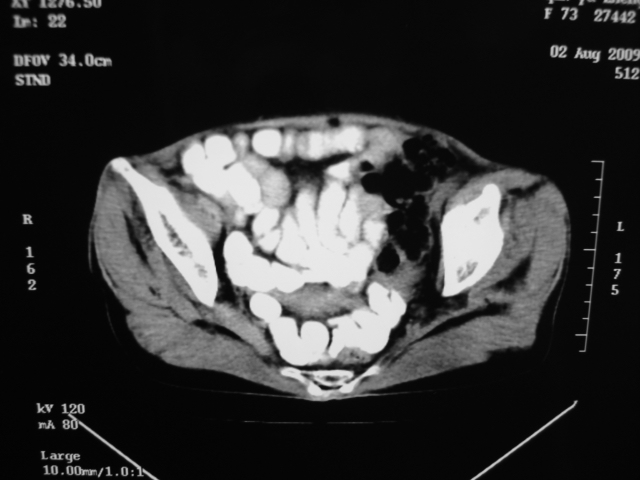

同事奶奶,73岁,腹痛一年,夜晚较重,潜血+++,拒绝增强,考虑左肾ca并腹膜后转移;请各位老师帮忙看看,谢谢!

左肾癌侵及输尿管上段,腹膜后多发淋巴结转移,脾脏钙化灶。至于潜血+++,要考虑消化道病变,本次ct片肠腔未见明显异常。

潜血+++是尿还是便?如果是便,则考虑肾癌侵犯降结肠可能。

1)考虑左肾癌侵犯肾盂并腹膜后淋巴结转移。2)脾脏钙化灶。

查查一胸部,不除外肺癌伴左侧肾上腺,腹膜后淋巴结及左肾转移.